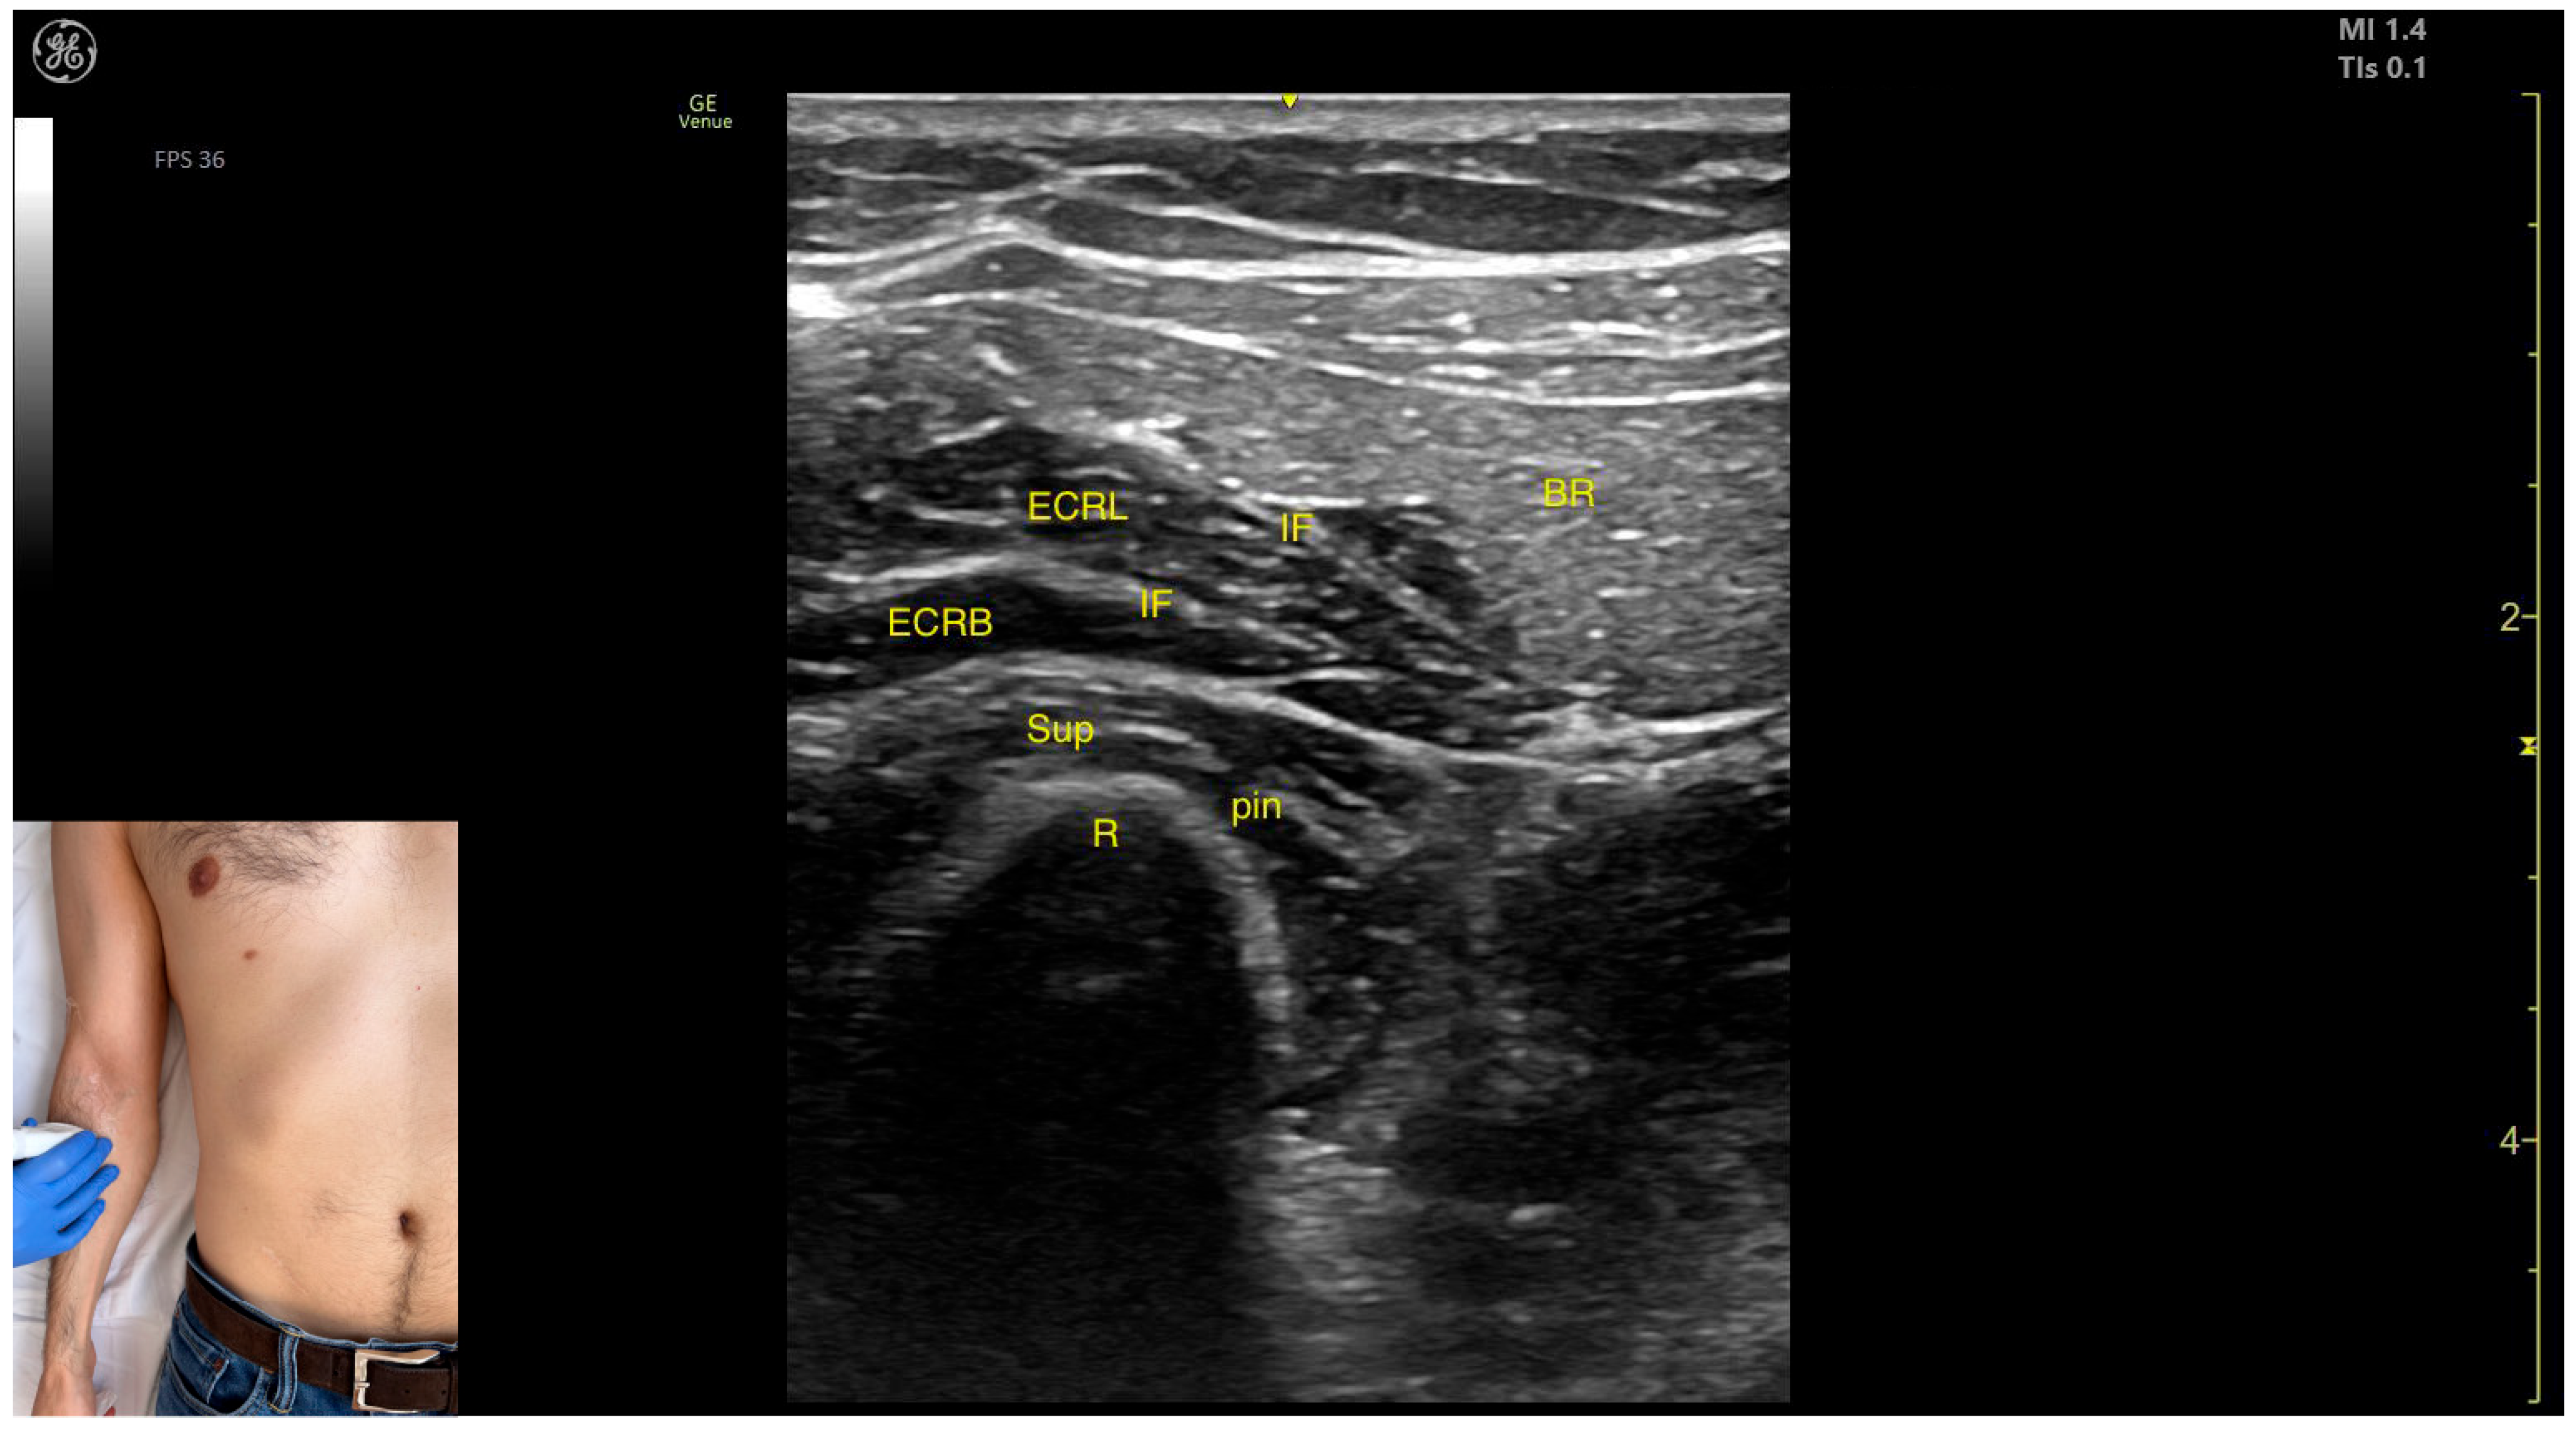

2.10. Brachioradialis (BR)

2.10.1. Overview

2.10.2. The Arm Compartment

Ultrasound Identification

Key Anatomical Landmarks

- Muscle position: It represents the most superficial muscle mass on the anterolateral surface of the arm at this level.

- Innervation: The radial nerve is located deep within the muscle, enclosed in the intermuscular fascia that separates the BR from the Brach muscle.

- External fascia: The BR has a pronounced fascia that separates it from both the Brach and the subcutaneous plane during BoNT-A injections.

- Dynamic evaluation: During dynamic evaluation, distal scanning toward the lateral epicondyle reveals the division of the radial nerve into its superficial branch and deep branch (posterior interosseous nerve), with the deep branch continuing along the anterolateral proximal third of the forearm.

2.10.3. The Forearm Compartment

- Muscle position: It represents the most superficial muscle mass at this level.

- External fascia: It has a thin intermuscular fascia that separates it from the extensor carpi radialis longus muscle, located deep to it.

- Dynamic evaluation: During dynamic evaluation, the BR can be differentiated from the extensor carpi radialis longus by performing wrist extension and abduction maneuvers with the forearm in pronation, during which contraction of the extensor carpi radialis longus is observed (Video S4). Contraction is visible both in the arm and forearm during elbow extension maneuvers, with the forearm positioned midway between supination and pronation.

2.10.4. Clinical Implications and Injection Strategy

- The transducer is placed transversely on the anterolateral surface of the arm, approximately 2–3 cm proximal to the lateral epicondyle.

- The transducer is placed transversely on the anterolateral surface of the forearm, approximately 2–3 cm distal to the lateral epicondyle.